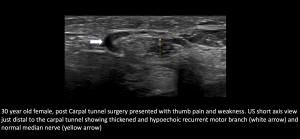

5.Recurrent Median branch Pathology